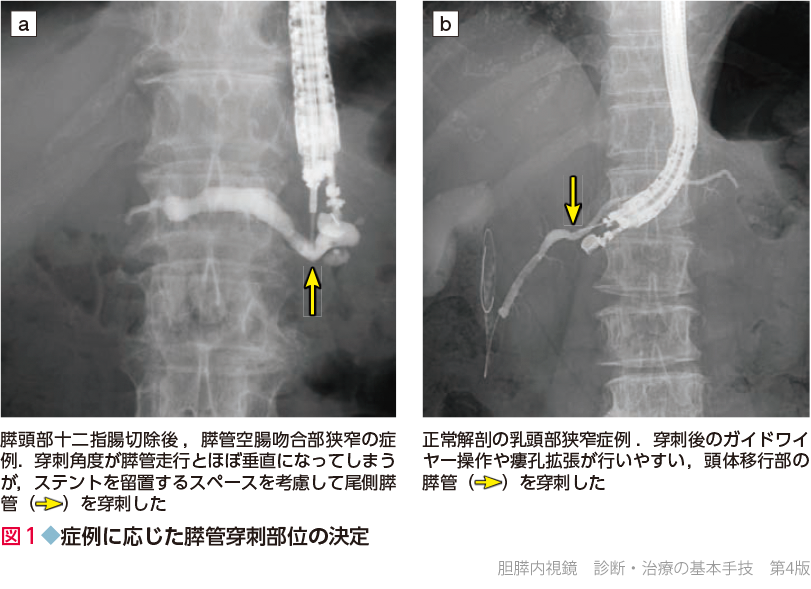

胆膵内視鏡の診断・治療の基本手技 第3版 | 糸井 隆夫 |本。胆膵内視鏡 診断・治療の基本手技 第4版 | 糸井 隆夫 |本 | 通販。胆膵内視鏡の診断・治療の基本手技 第3版 | 糸井 隆夫 |本。国産米粉のホットケーキミックス☆驚くほどもっちり☆MOLINAGA☆2袋セット。胆膵内視鏡 診断・治療の基本手技 第4版 - 羊土社。最先端治療 胆道がん・膵臓がん – 法研。裁断済(バラバラ)の本です。胆膵内視鏡の診断・治療の基本手技 第3版 - 羊土社。。胆膵内視鏡 診断・治療の基本手技 第4版 - 羊土社。胆膵内視鏡でサポートバンドを導入 - 事例紹介|Medicle。内視鏡センター|社会医療法人三栄会 ツカザキ病院。胆膵内視鏡の診断・治療の基本手技 改訂2版」付録DVD。胆膵内視鏡の診断・治療の基本手技 - 羊土社。裁断済みの為、状態が悪いとしていますが、書き込み等ございません。使い方の分かる方のご購入をお願いいたします。JDDWで売上1位を獲得した話題の新刊『これで完璧!胆膵内視鏡の